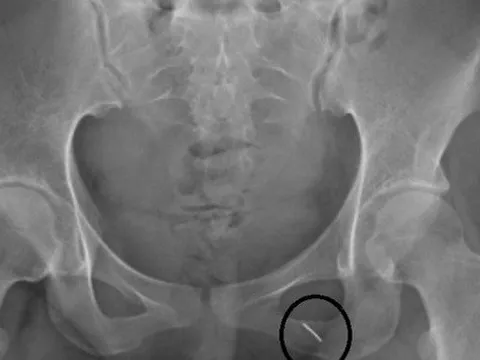

Phòng thượng mã phong cho chú rể, cô dâu bị kim đâm xuyên mông

Chiếc kim gài gấu váy cưới được các cụ mách cho cô dâu cứu chồng đêm tân hôn nếu không may bị thượng mã phong đã khiến cô dâu phải đến viện ngay đêm tân hôn